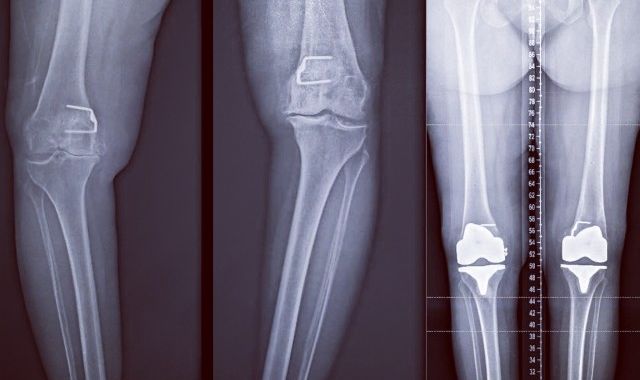

Naturally Aligned Computer Assisted Knee Replacement

Computer assisted Surgery (CAS) has now been around for almost 20 yrs. in various forms. With the...

Alternate Alignment Technique for Total Knee Replacement

Alternate alignment is gaining popularity amongst orthopaedic surgeons. The alternate alignment...

Computer assisted Knee Arthroplasty - Dr. Kaushik Hazratwala

Knee replacements have been traditionally been done by bony alignment jigs. That is the surgeon...